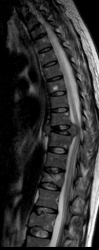

Вот другой режим:

Что при Т1 что при Т2 нет изменения сигнала, идет уплотнение структуры позвонков, Натечник исключается ибо его при таких изменениях было бы четко видно и на рентгенограммах.

Я тоже считаю, что это не натечник. Позвонок же сильно расплющился, ширина его увеличилась, вот паравертебральные ткани чуть-чуть и выступают.